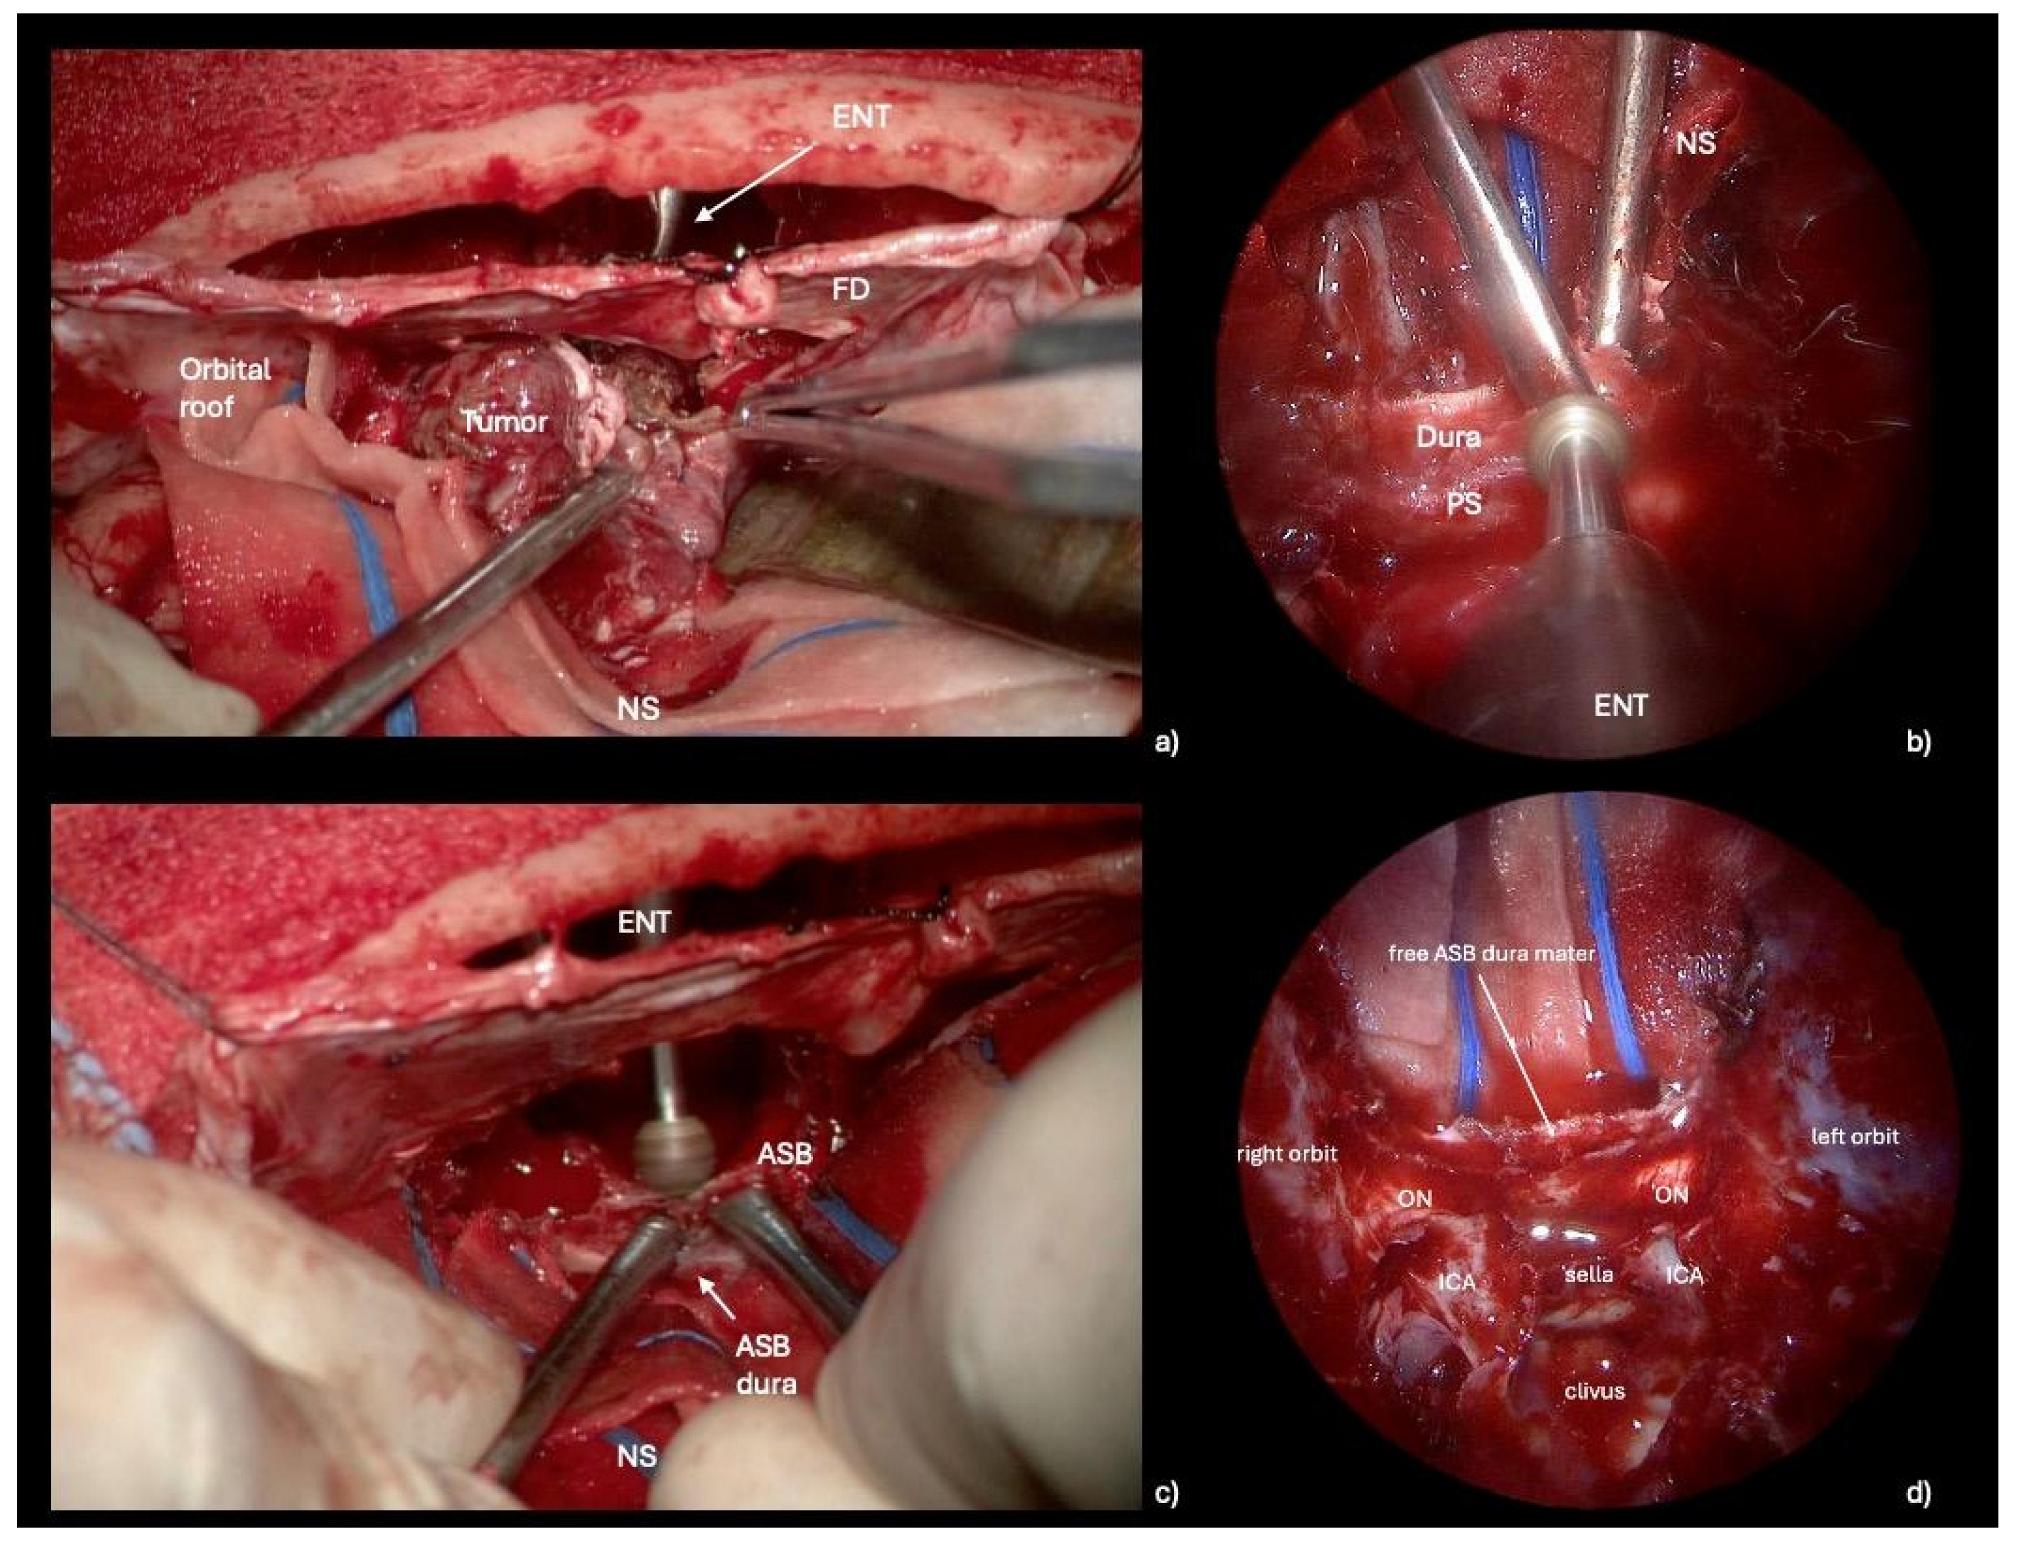

Figure 3. Intraoperative propedeutical steps to anterior cranial base reconstruction. (a) Microscopic transcranial view of simultaneous tumor removal: the ENT specialist and the neurosurgeon work together, utilizing multiportal access. (b,c) Endoscopic endonasal and microscopic transcranial views showing the crucial step of drilling the planum sphenoidale: by removing the bone, the dura mater of the anterior cranial fossa is exposed, facilitating its suturing to the pericranial flap during the reconstructive transcranial phase. (d) Final endoscopic view with the anterior cranial base dura mater exposed. Abbreviations. ENT: otolaryngologist; FD: frontal dura; NS: neurosurgeon; PS: planum sphenoidale; ASB: anterior skull base; ON: optic nerve; ICA: internal carotid artery.

2.2.4. Reconstruction Phase

The key to performing an optimal skull base reconstruction is to properly dissect the epidural space over the orbital roof laterally and the ethmoidal roof/planum sphenoidale posteriorly. Specifically, we recommend lightly drilling the lateral and posterior edges of the craniectomy via the endonasal corridor. Simultaneously, under microscopic view, the neurosurgeon dissects the epidural space while protecting the dura of the ASB, assisting the ENT specialist during this delicate phase. By removing the bone, the dura mater of the anterior cranial fossa is exposed, facilitating its suturing to the PF during the transcranial reconstruction. (Figure 3, Video S1). A transcranial approach is employed to repair the anterior skull base defect with a PF secured using button sutures. A hemostatic sealing matrix (e.g., TachoSil®) can be placed underlay (intradural) to stabilize the suture between the PF and the dura mater of the anterior cranial base. Concurrently, endoscope-assisted ASB reconstruction is performed. Additionally, connective tissue, such as temporal fascia or fascia lata, is applied in an overlay fashion to reinforce the reconstruction endonasally. Specifically, the fascia lata is carefully positioned as an overlay graft, covering the defect area to reinforce the primary reconstruction performed with the PF. (Figure 4). The surgical procedure is shown in Video S1.